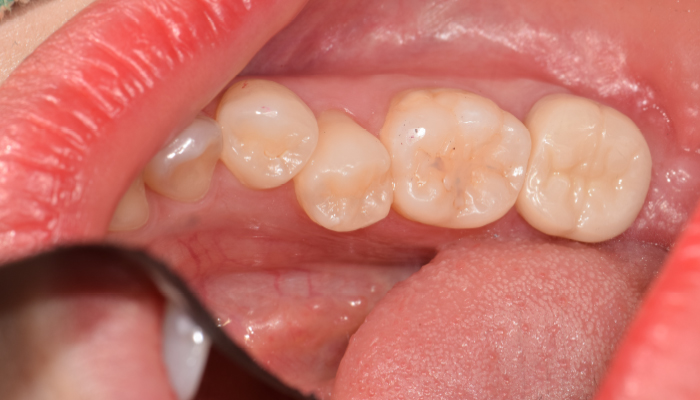

충치치료 전후 사례

치료 후

• 치료전

치료후